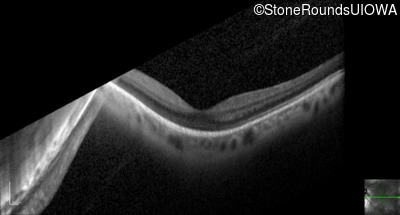

Optical Coherence Tomography - Right - 20/40 +2

Exemplar / OCT Stack